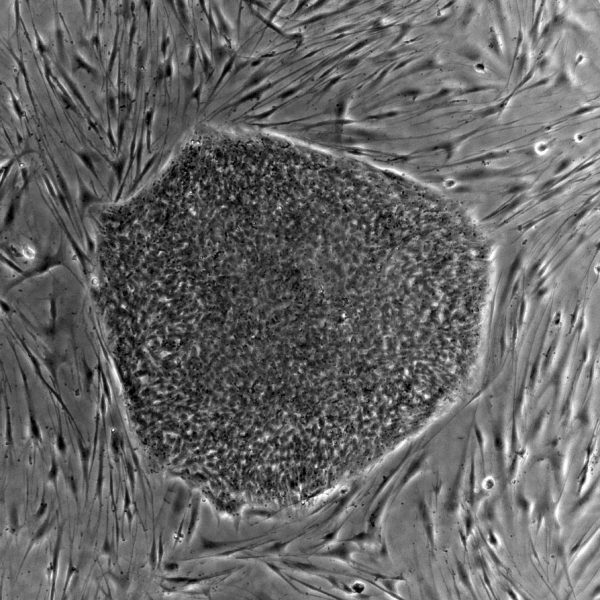

Pierre-Antoine Faye vient de publier l’article « Optimized protocol to generate spinal motor neuron cells form induced pluripotent stem cells from Charcot-Marie-Tooth patients » dans le journal Brain Sciences.

L’objectif était de développer un protocole reproductible, robuste et facile à mettre en place afin d’obtenir des motoneurones spinaux à partir de hiPSCs de patients CMT. En effet, dans le cas des neuropathies périphériques comme la maladie de CMT, ce sont ces motoneurones qui sont altérés mais il sont difficiles à étudier. Afin de pouvoir envisager de comprendre les mécanismes pathologiques du CMT et développer de nouvelles stratégies thérapeutiques, obtenir efficacement des motoneurones est important. Plusieurs protocoles sont disponibles pour différencier les hiPSCs en neurones mais leur efficacité reste faible pour les patients CMT, mais grâce à ce protocole nous avons pu générer des motoneurones spinaux en 20 jours avec un taux de réussite de 80% impliquant des concentrations de facteurs et des moments cruciaux pour induire la différenciation. Cette méthode de génération des motoneurones in vitro nous permet d’envisager un avenir prometteur dans la compréhension des mécanismes et le criblage de médicaments.